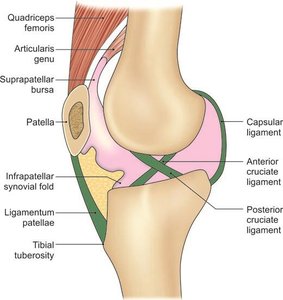

Fibrous capsule: Encloses the joint.

Ligamentum patellae: Connects the patella to the tibia.

Anterior and posterior cruciate ligaments: Prevent anterior and posterior displacement of the tibia.

Synovial Membrane and Bursae

The synovial membrane lines the capsule of the knee joint, except posteriorly where it is reflected by the cruciate ligaments. It forms a common covering for both ligaments. Numerous bursae surround the knee, reducing friction between tendons, ligaments, and bone.

Anterior bursae: Subcutaneous prepatellar, subcutaneous infrapatellar, deep infrapatellar, suprapatellar.

Anterior: Quadriceps femoris, patella, ligamentum patellae.

Posterior: Popliteal vessels, tibial nerve, heads of gastrocnemius.

Locking and unlocking: Locking allows the knee to remain extended with minimal muscular effort, primarily through medial rotation of the femur. Unlocking is achieved by the popliteus muscle, which laterally rotates the femur.

Unlocking muscle: Popliteus.